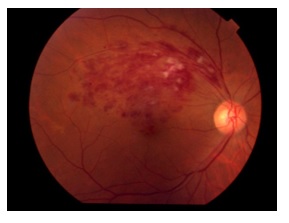

網膜静脈閉塞症

網膜静脈閉塞症は網膜の静脈が血栓などにより閉塞し、出血する疾患です。黄斑部に浮腫が生じる場合(黄斑浮腫)があり、その場合視力が低下することがあります。黄斑浮腫の治療としてステロイドや抗VEGF薬の注射などがあります。また、血流の不良の場所に網膜光凝固(レーザー治療)を行うこともあります。硝子体出血を起こした場合には硝子体手術を行うこともあります。